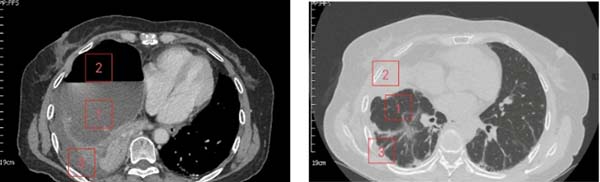

术后1月胸部CT纵膈窗/肺窗

1、充分复张的肺;2、空腔消失;3、脓胸消失。